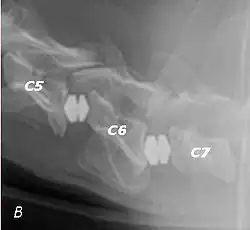

The disease tends to be gradually progressive. Symptoms such as weakness, ataxia, and dragging of the toes start in the rear legs. Dogs often have a crouching stance with a downward flexed neck. The disease progresses to the front legs, but the symptoms are less severe. Neck pain is sometimes seen. Symptoms are usually gradual in onset, but may progress rapidly following trauma.[6] X-rays may show misaligned vertebrae and narrow disk spaces, but it is not as effective as a myelogram, which reveals stenosis of the vertebral canal. Magnetic resonance imaging has been shown to be more effective at showing the location, nature, and severity of spinal cord compression than a myelogram.[7] Treatment is either medical to control the symptoms, usually with corticosteroids and cage rest, or surgical to correct the spinal cord compression. The prognosis is guarded in either case. Surgery may fully correct the problem, but it is technically difficult and relapses may occur. Types of surgery include ventral decompression of the spinal cord (ventral slot technique), dorsal decompression, and vertebral stabilization.[8] One study showed no significant advantage to any of the common spinal cord decompression procedures.[9] Another study showed that electroacupuncture may be a successful treatment for Wobbler disease.[10] A new surgical treatment using a proprietary medical device has been developed for dogs with disc-associated wobbler disease. It implants an artificial disc (cervical arthroplasty) in place of the affected disc space.[11]

Wobbler disease is definitively diagnosed by x-ray, nuclear scintigraphy or bone scan. X-rays will show channel widening or filling the easiest and are often most cost-effective to horse owners. X-rays will also show any structural anomaly, arthritis, facet remodeling, or bone spurs present. Preliminary diagnosis can be made by ultrasound but x-rays are needed to measure the true depth of facet involvement. For extent of damage to associated structures, veterinarians may opt to have the horse undergo a bone scan or nuclear scintigraphy.